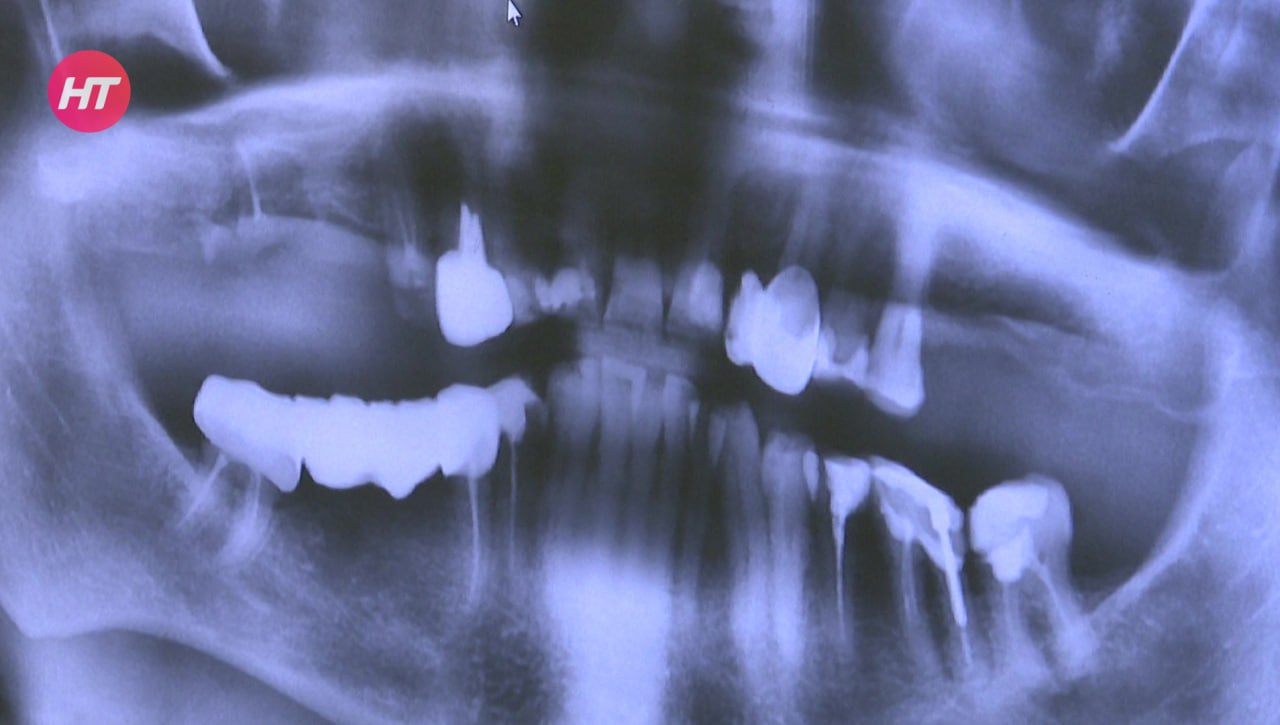

Новгородским участникам СВО начали оказывать услуги по зубопротезированию

Бесплатное протезирование будут делать на базе Новгородской областной больницы – это новая региональная форма поддержки ветеранов СВО. Попасть на приём стоматолога можно в день еженедельной диспансеризации для бойцов. Самый простой способ – обратиться в фонд «Защитники Отечества» или к своему социальному координатору.